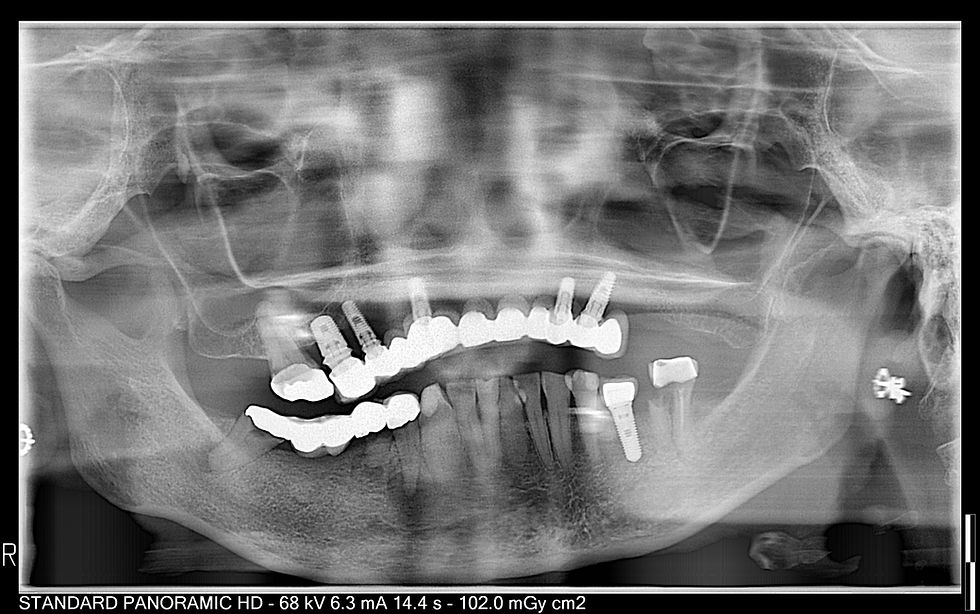

SmileOn4 implants are an advanced custom dental restoration technique used to replace an entire arch of missing teeth (upper or lower) using just four or more strategically placed dental implants. This method provides a permanent, stable, and natural-looking solution without the need for individual implants for each missing tooth.

Four implants support a full arch of prosthetic teeth

Rear implants are often angled to maximize bone contact and avoid sinus cavities or nerves

Suitable for patients with low bone volume, often eliminating the need for bone grafting

Offers same-day teeth—temporary teeth may be placed immediately after implant surgery